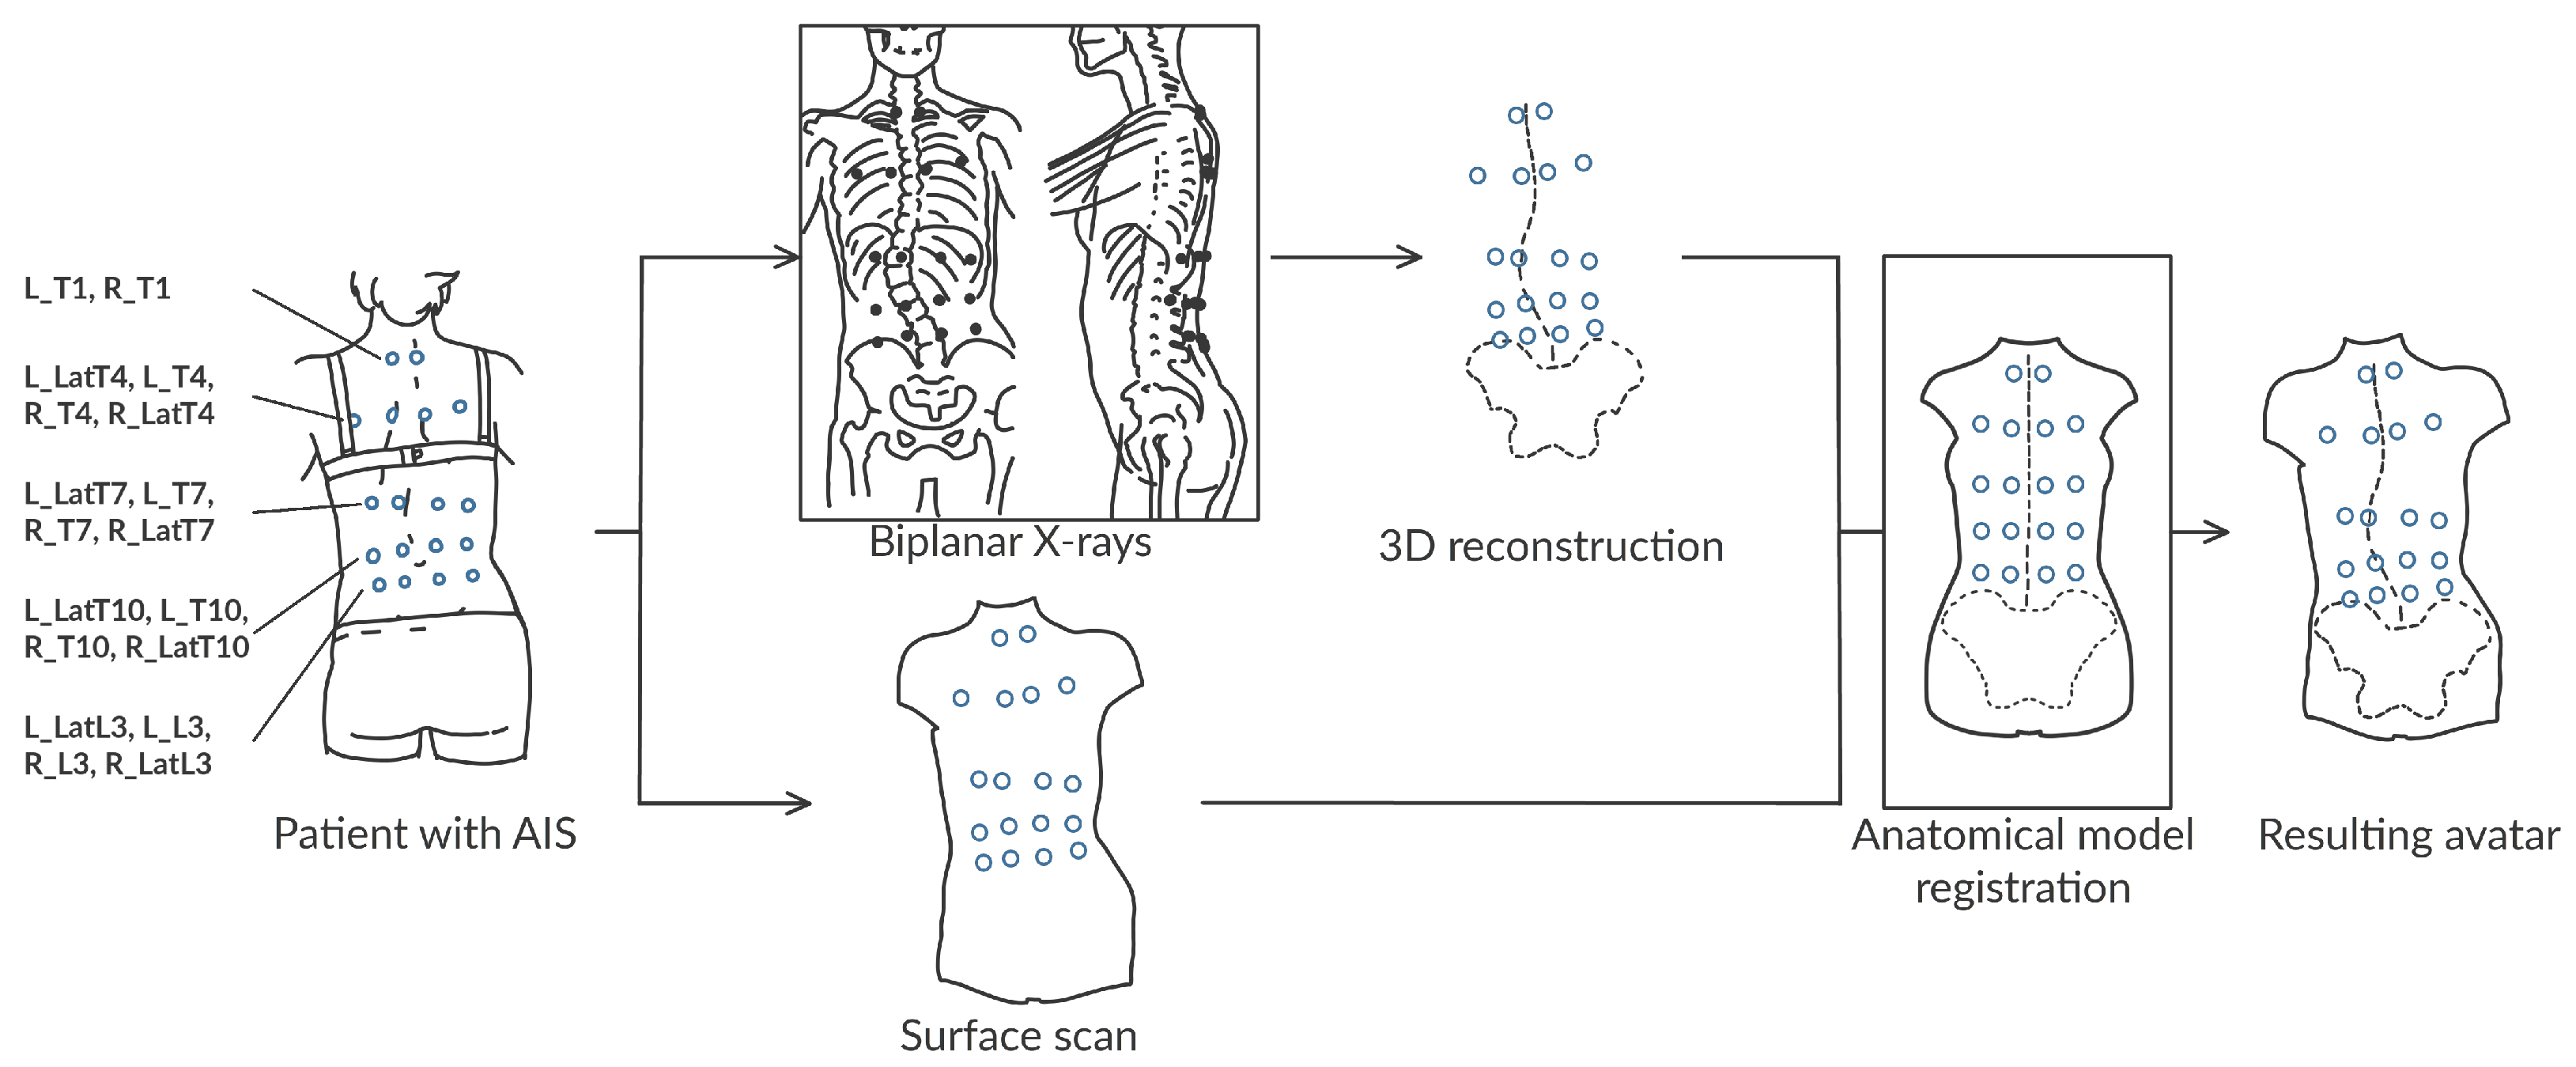

:1. Introduction

2. Materials and Methods

2.1. Collected Data

- A biplanar X-ray of their trunk made with an EOS imaging system

- A surface scan of the back using an Occipital Structure Sensor Mark II (XRPro, LLC, Saratov)

2.2. Data Processing

2.3. The Subject-Specific Kinematic Model